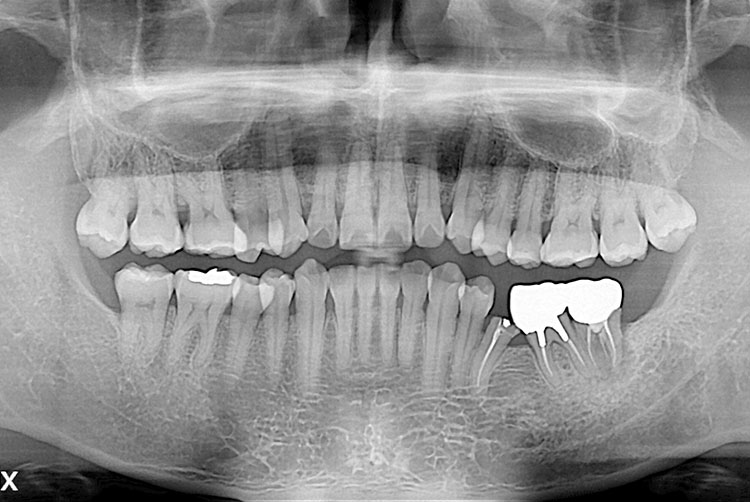

[임플란트] 임플란트

21.10.20.jpg

치료후 : 2021-10-20

세종치과는 많은 환자와 다양한 케이스를 바탕으로 항상 편안한 임플란트 수술을 제공하고자 노력하고,

오래동안 튼튼히 쓸 수 있는 임플란트 수술을 가장 큰 목표로 삼고 있습니다